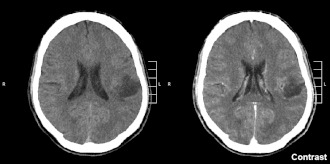

| Glioma no lobo parietal de segundo grau em CT scan cerebral. | |

Glioma é um tumor de células gliais, células que protegem, nutrem e dão suporte aos neurônios, logo podem ocorrer no encéfalo, na medula espinhal ou mesmo junto a nervos periféricos. São responsáveis por aproximadamente 30% de todos os tumores do sistema nervoso central e por 80% dos tumores malignos iniciados no cérebro.[1]